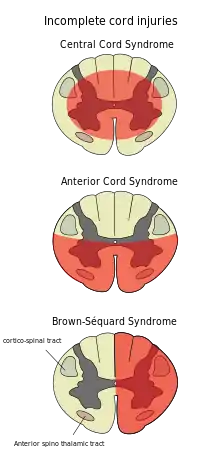

Central cord syndrome

Central cord syndrome, almost always resulting from damage to the cervical spinal cord, is characterized by weakness in the arms with relative sparing of the legs, and spared sensation in regions served by the sacral segments.[24] There is loss of sensation of pain, temperature, light touch, and pressure below the level of injury.[25] The spinal tracts that serve the arms are more affected due to their central location in the spinal cord, while the corticospinal fibers destined for the legs are spared due to their more external location.[25] The most common of the incomplete SCI syndromes, central cord syndrome usually results from neck hyperextension in older people with spinal stenosis. In younger people, it most commonly results from neck flexion.[26] The most common causes are falls and vehicle accidents; however other possible causes include spinal stenosis and impingement on the spinal cord by a tumor or intervertebral disc.[27]

Anterior spinal artery syndrome

Anterior spinal artery syndrome also known as anterior spinal cord syndrome, due to damage to the front portion of the spinal cord or reduction in the blood supply from the anterior spinal artery, can be caused by fractures or dislocations of vertebrae or herniated disks.[25] Below the level of injury, motor function, pain sensation, and temperature sensation are lost, while sense of touch and proprioception (sense of position in space) remain intact.[28][26] These differences are due to the relative locations of the spinal tracts responsible for each type of function.

Brown-Séquard syndrome

Brown-Séquard syndrome occurs when the spinal cord is injured on one side much more than the other.[29] It is rare for the spinal cord to be truly hemisected (severed on one side), but partial lesions due to penetrating wounds (such as gunshot or knife wounds) or fractured vertebrae or tumors are common.[30] On the ipsilateral side of the injury (same side), the body loses motor function, proprioception, and senses of vibration and touch.[29] On the contralateral (opposite side) of the injury, there is a loss of pain and temperature sensations.[27][29]Spinothalamic tracts are in charge for pain and temperature sensation and because these tracts cross to the opposite side and above the spinal cord there is loss on the contralateral side.[31]